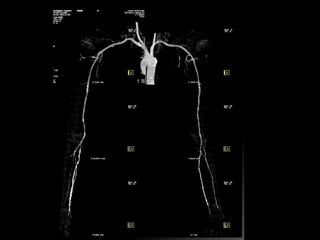

• There is extensive thrombosis of infrarenal segment of aorta, extending upto its bifurcation; into both common iliac

arteries causing total block in aorta and only minimal opacification of common ileac arteries bilaterally.

• Left renal artery is also blocked.

• Left kidney is small in size.

• Inferior mesenteric artery is not opacified.

• Bilateral external and internal iliac arteries reveal good contrast opacification from collateral of lumbar, intercoastal

and inferior epigastric arteries.

• Its superior ventral branches (i.e) coeliac and superior mesenteric artery are normal.

• Right renal artery is normal.

• CT scan of reveal Lehriche’s syndrome seen as block in infra renal abdominal aorta with blocked left renal artery.